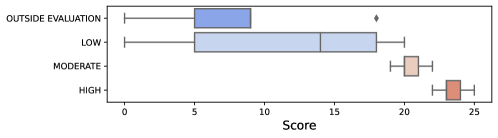

51 reports were evaluated (Figure 5); 5 of them were excluded due to extreme artifacts (n=1, =0) and ventricular extrasystole (n=4, 10.25 ± 5.5). Of the remaining 46 reports, 17 were categorized as high (23.29 ± 1.04), 14 as moderate (20.28 ± 0.99), and 15 as low (11.20 ± 7.76) in terms of interpretability. The "±" symbol represents the mean and standard deviation of validation scores, respectively. A total of 31 reports were identified as acceptable.

In terms of overall counterfactual sparsity, our clinical approach demonstrated lower sparsity (0.19) compared to the XGB feature, which had a sparsity of 0.33. For a clearer understanding of sparsity on individuals, please refer to Figure 6. Patient-wise differences can be observed by comparing clinical and XGB boxplots. The general sparsity in XGB is evident in the figure, although some cases displayed even lower sparsity than their clinical-weighted counterparts.

In the alignment of blind evaluations and identified clues, we obtained scores of 0.83 ± 0.12 for high-quality reports, 0.57 ± 0.10 for moderate-quality reports, and 0.22 ± 0.24 for low-quality reports. We observed that a many of the low-quality reports were attributed to incorrect peak detection, which inevitably resulted in their low-quality classification. Moreover, these low-quality reports often contained labels that were inconsistent with our blind evaluations and the original labels.